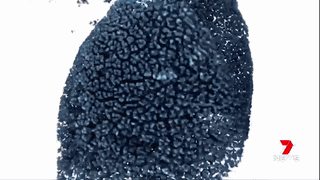

澳洲的科學家們通過運用納米技術,將“基因沉默”(gene silencing)藥物運送至腫瘤細胞中來治療胰腺癌。

藥物已經在擁有和人類相仿的瘢痕組織的小鼠身上進行試驗,并獲得成功。